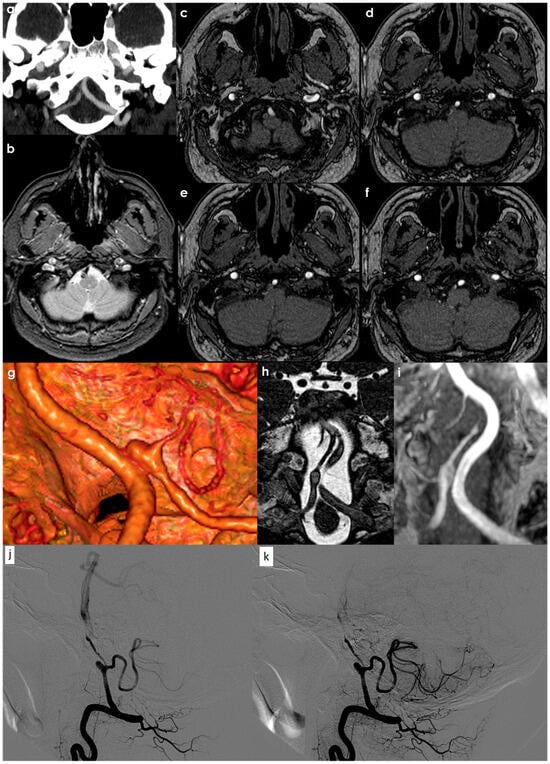

Following an intracranial arterial dissection, some patients may experience a remodeling of their vascular structures, leading to the formation of dolichoectatic or fusiform aneurysms that remain intact without rupturing. The progression of posterior circulation dissecting aneurysms, especially those that arise without accompanying stroke or hemorrhage, was thoroughly examined by Kobayashi et al. []. In their investigation involving 113 patients—predominantly asymptomatic or presenting with pain—over an average follow-up of 2.9 years, the researchers observed that 97% of the subjects remained clinically stable, and 80% of the aneurysms exhibited no morphological changes. Only 4% of the cases showed aneurysm enlargement, which correlated strongly with clinical worsening. Hence, it is reasonable to conclude that patients with posterior circulation dissecting aneurysms who do not present with stroke or hemorrhage can typically be treated conservatively, reserving interventional procedures for situations involving mass effects or lesion growth. A rapid process of vessel remodeling and repair is characteristic of both intracranial and extracranial dissection. In Figure 4, an example of the evolution of a VAD is illustrated.

Figure 4.

The right V4 VAD involving the takeoff of the PICA in the acute phase: panel (a) (CTA reconstructed in a coronal oblique plane with MIP/MPR protocol); panel (b) (T2* MRI with the hypointense hematoma causing focal VA occlusion and positive remodeling); panels (c–f) (MRA source images showing the absence of flow in the dissected segment including the PICA origin). In the 10-day CTA follow-up (panel (g)), the partial recanalization of the dissection segment with a PICA aneurysm is shown using a 3D reconstruction in a volume rendering. The corresponding MRI (panel (h), balance) and MRA (panel (i), coronal plane in MIP/MPR protocol) confirmed this finding, well evident in DSA from right VA injection in lateral view in early (panel (j)) and late arterial phase (panel (k)). A 20-day follow-up DSA illustrated, in lateral view, the aneurysm at the origin of the left PICA and the severe, irregular stenosis, of the post-PICA in the left V4 VA.